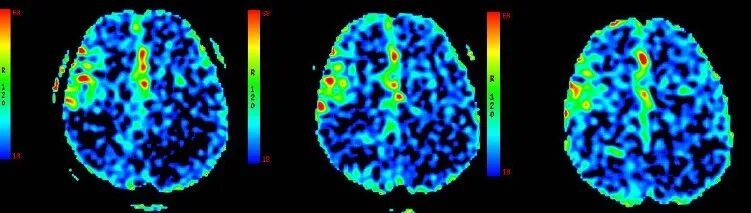

ASL

重要影像结论:3月前ASL示:左侧额颞顶枕叶、右侧颞枕叶血流灌注量明显减低。

重要影像结论:ASL示:原左侧额颞顶枕叶、右侧颞枕顶叶血流灌注量明显减低区范围较3月前明显增大。